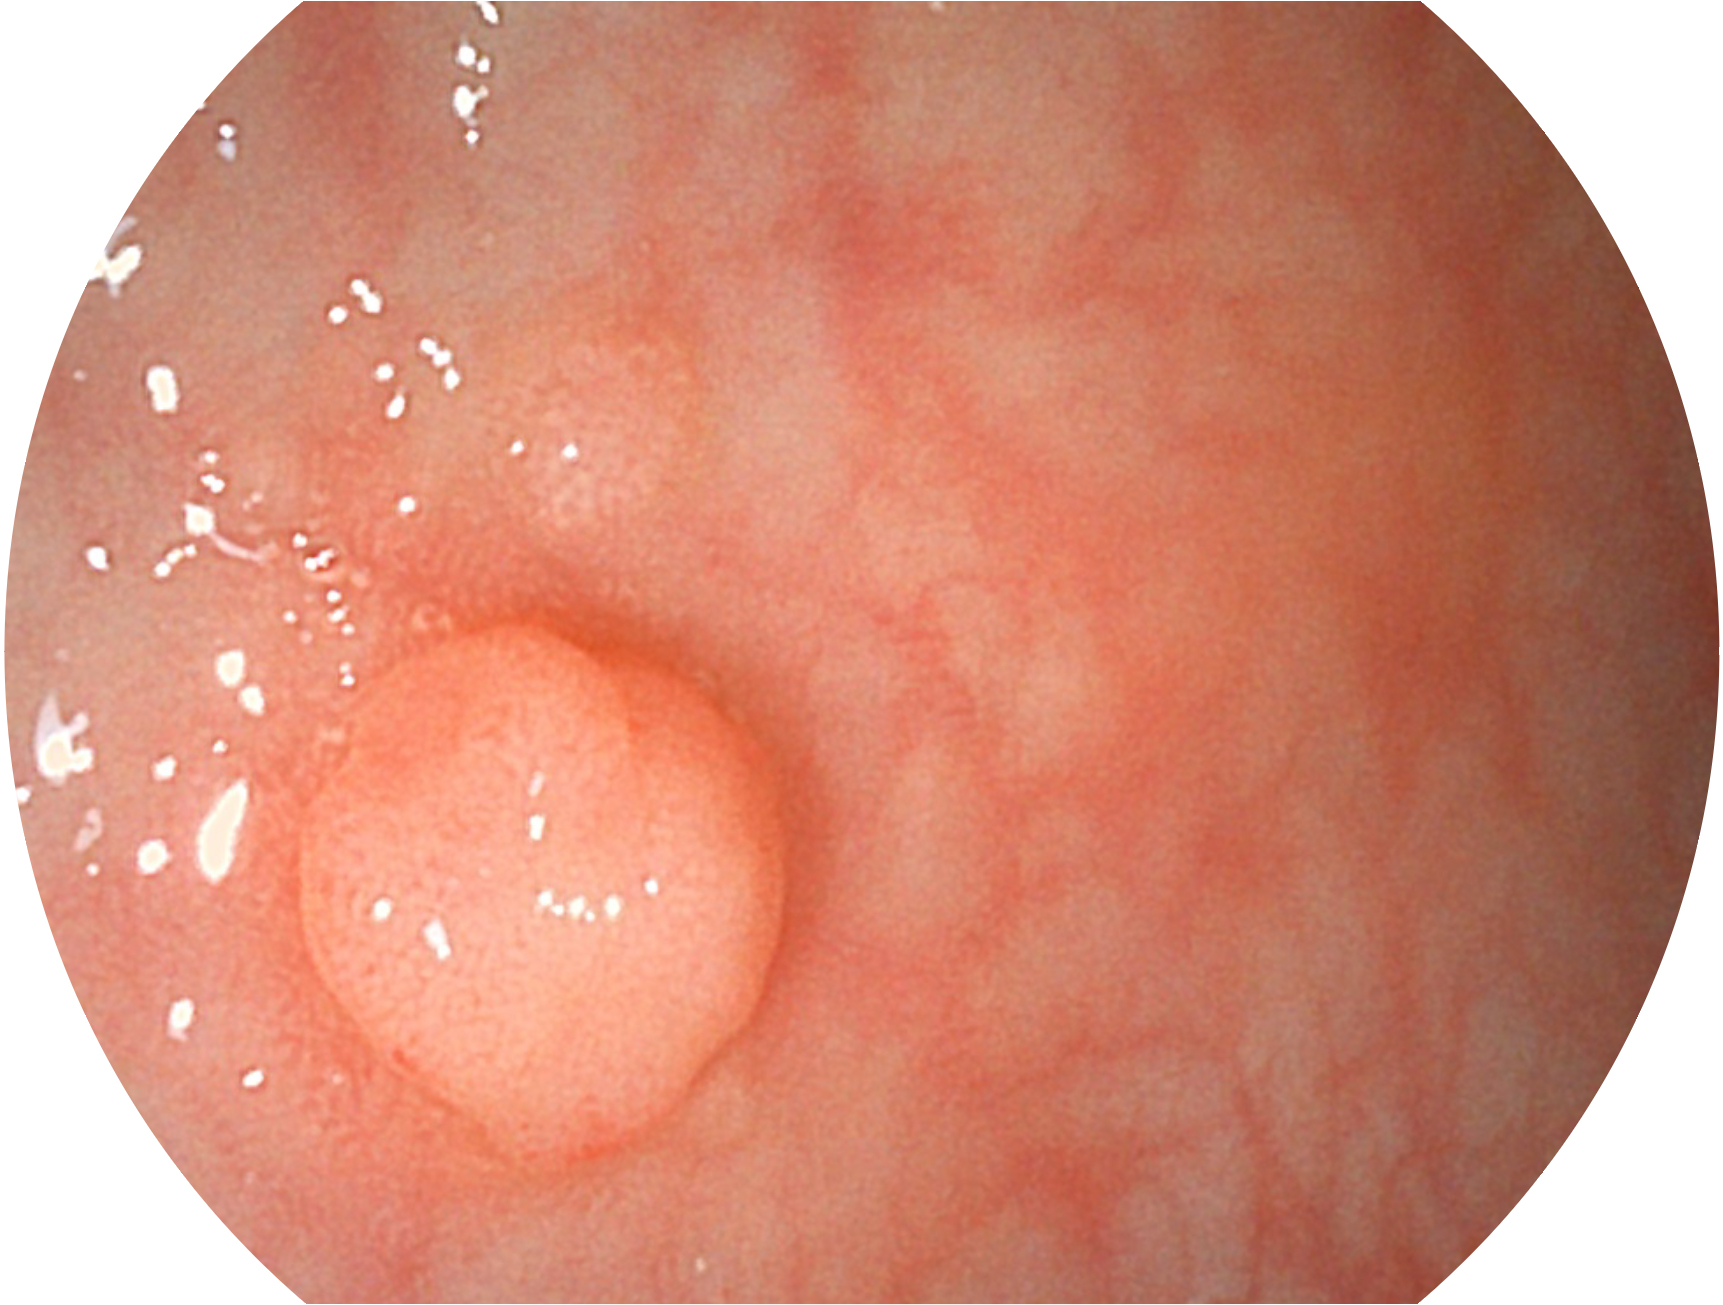

球速体育入口新开发的内镜染色技术,主要是基于多波长LED 光源的开发,VLS-55Q 四波长LED 光源是由四个不同颜色的LED光按照相应照明模式所规定的特定发光比例进行合束后形成,合束后形成的照明光的光谱由红光、绿光、蓝光及蓝紫光这四个不同的波段范围构成。具有更高光谱自由度,通过光谱比例的控制,实现了聚谱成像技术,英文全称为“Spectral Focused Imaging, SFI”,缩写为“SFI”和光电复合染色成像技术,英文全称为“Versatile Intelligent Staining Technology, VIST”,缩写为“VIST”。